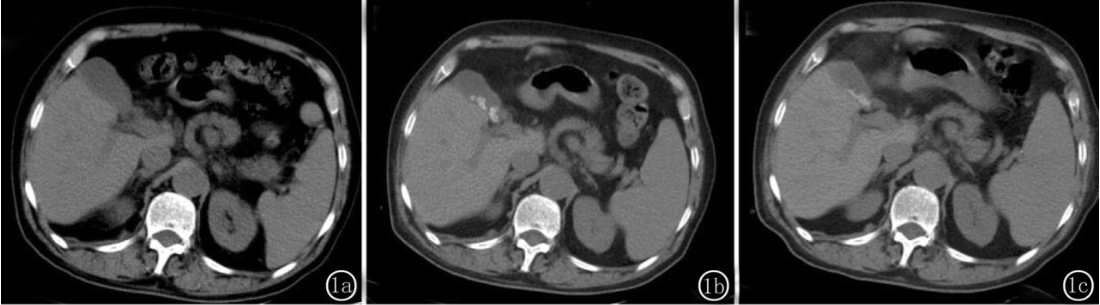

图1 男84岁。因创伤性蛛网膜下腔出血合并多发肋骨骨折。图1a 患者应用头孢曲松钠前胆囊内未发现结石。图1b 用药后( 10天) 胆囊内出现团块状高密度结石影。图1c 患者停用头孢曲松钠15 天后发现结石形态松散变淡。